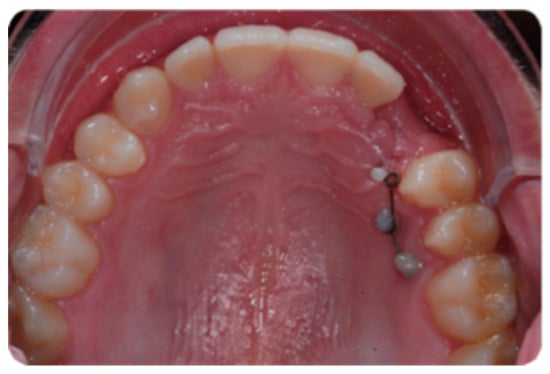

Figure 4 shows the first TAD approach for canine traction two mini-screws (Spider Pin 1.3 × 10 mm, HDC, Sarcedo, Italy) have been inserted. The sectional wire directly bonded on the TADs is a 0.18 SS Australian wire.

Figure 4.

Initial orthodontic vertical traction on a 0-18 SS wire.